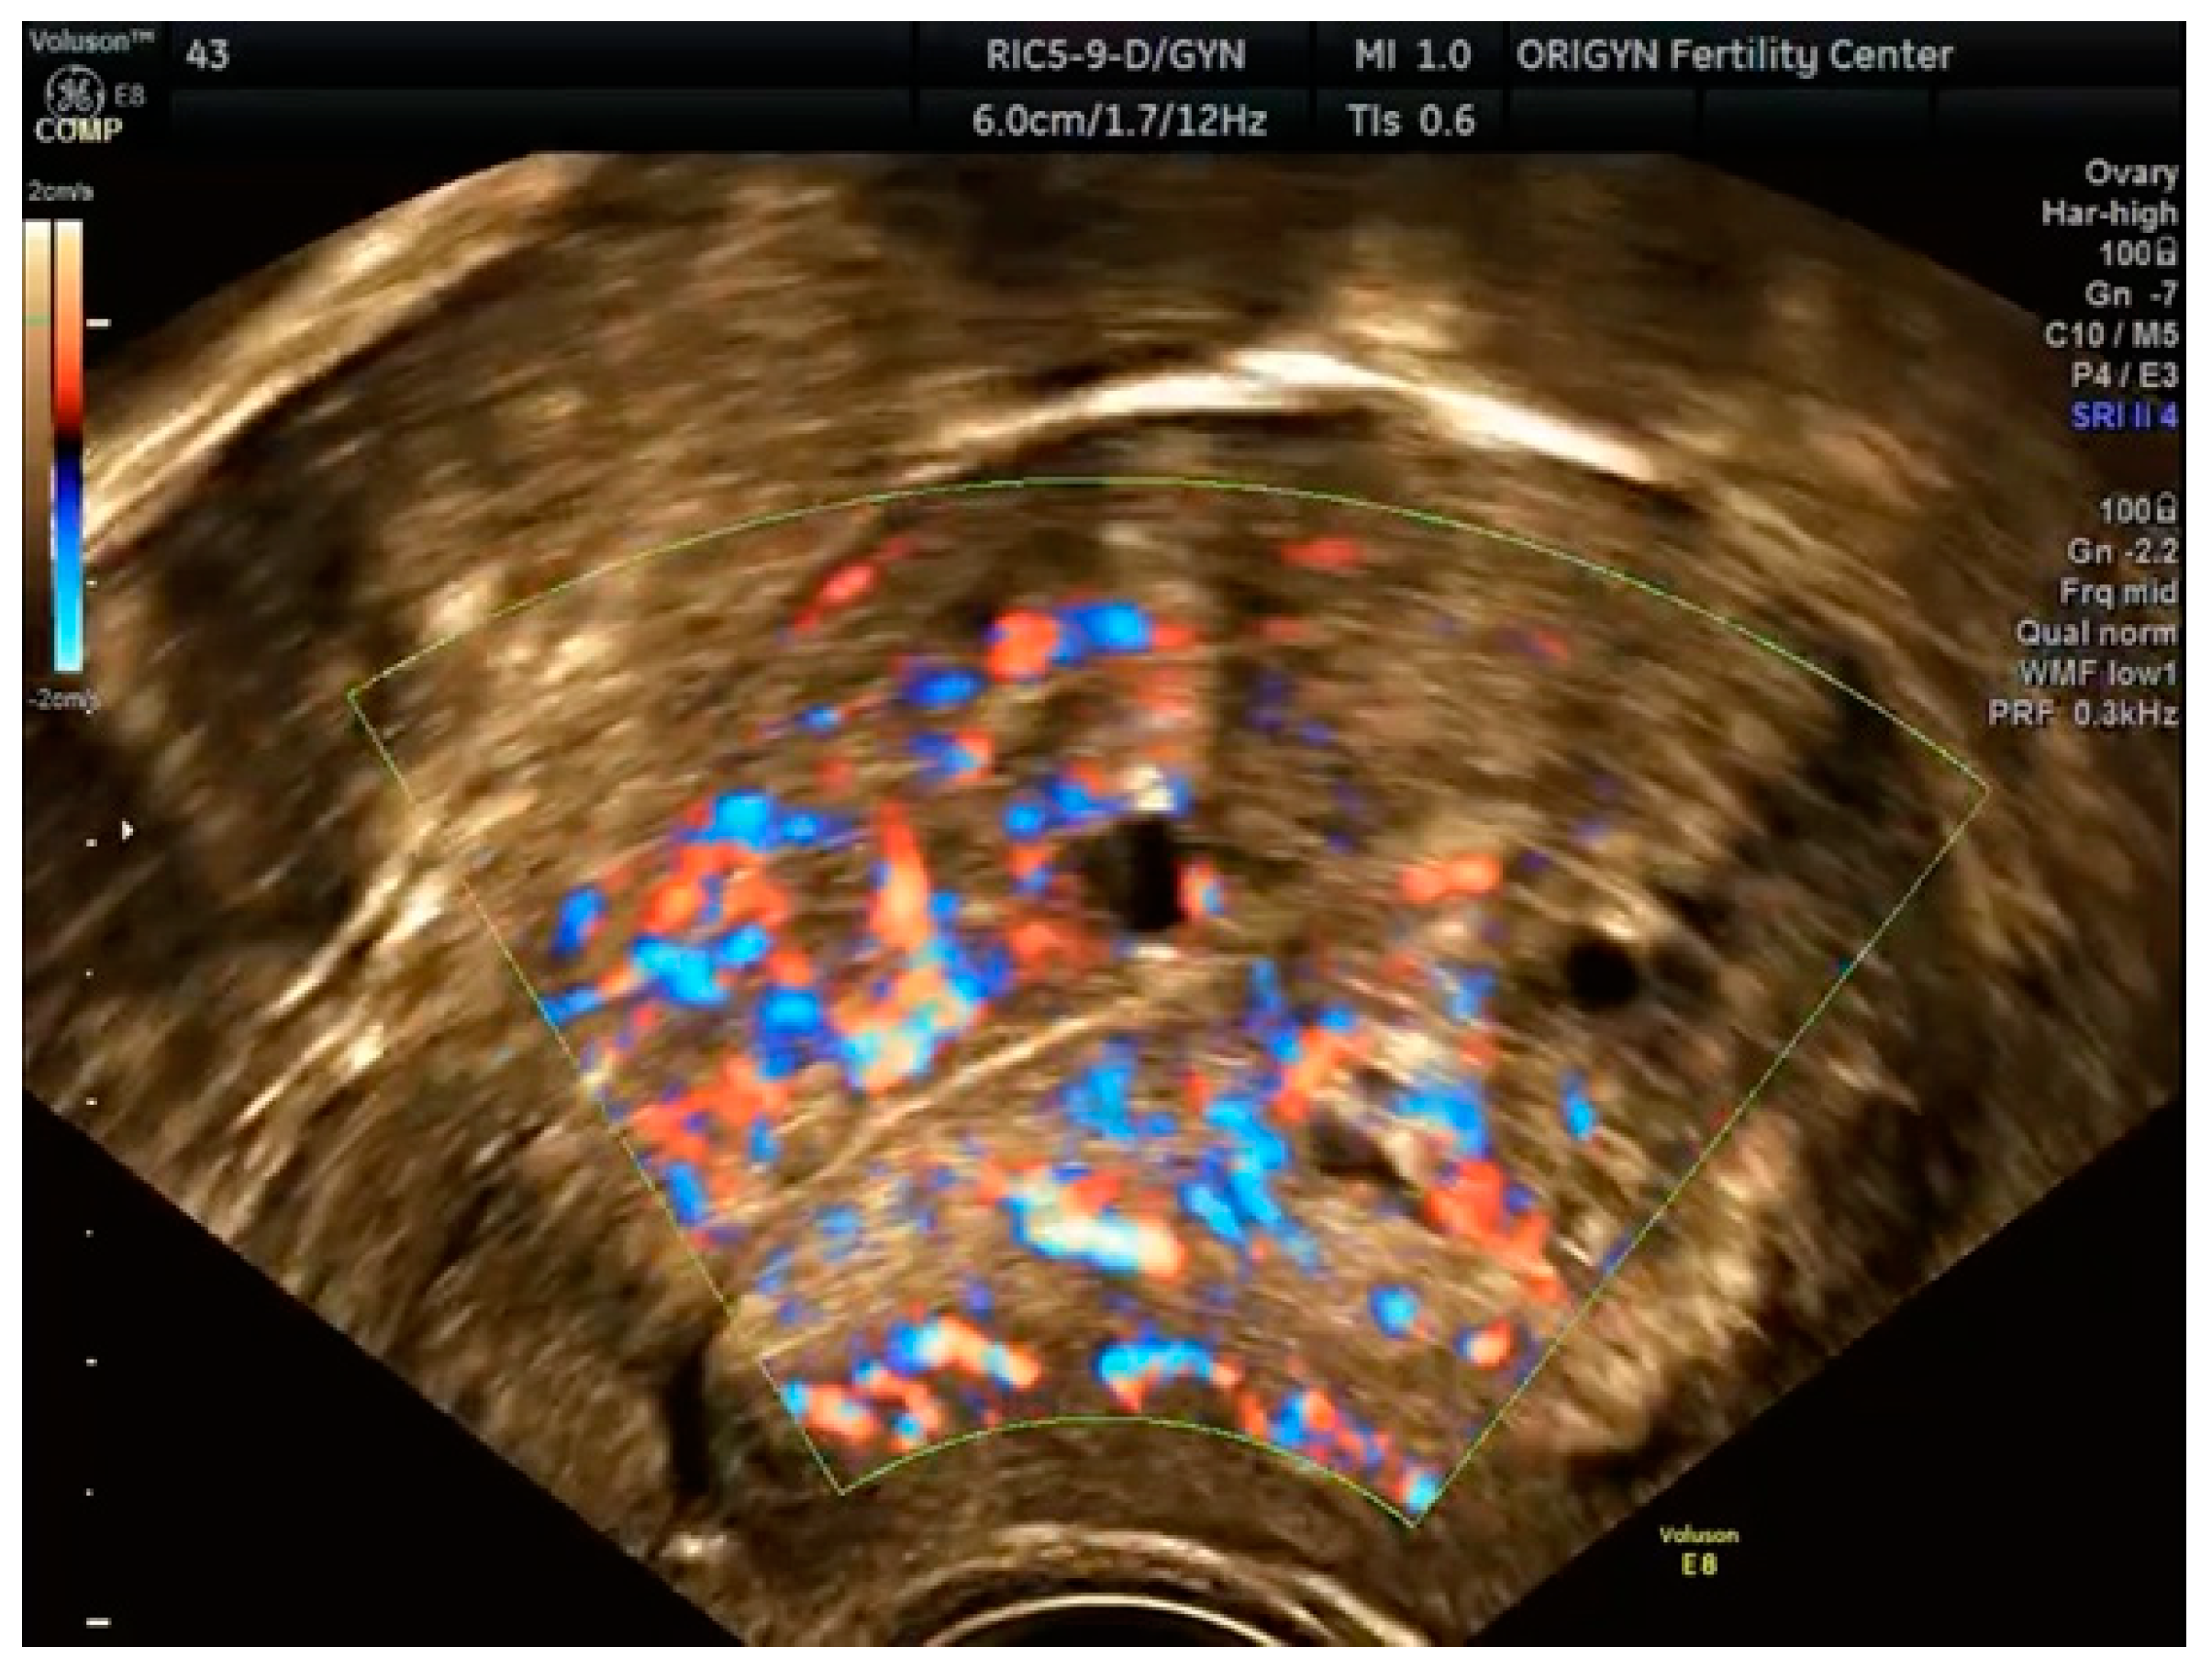

3.1. ADNEXA

3.2. Adenomyosis